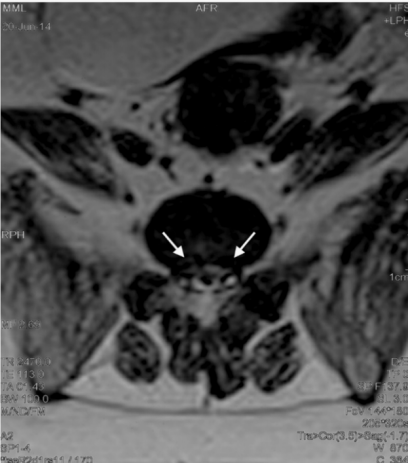

这只雌性混种犬就诊时情况令人揪心:后肢软弱无力,走路时膝盖弯曲变形,连最基本的爬楼梯都成了奢望,还出现了尿失禁症状。检查显示,它除了患有DLSS外,还伴有双膝骨关节炎。触诊时,腰骶部的疼痛反应明显,膀胱肿大,尾部张力减弱,种种迹象都表明病情已相当严重。

3. 精准注射将3000多万个细胞注入腰椎病变部位,同时在其膝关节内注入1500多万个细胞

1. 注射位置创新:选择椎间孔附近而非椎间盘内,为干细胞提供了更适宜的存活环境